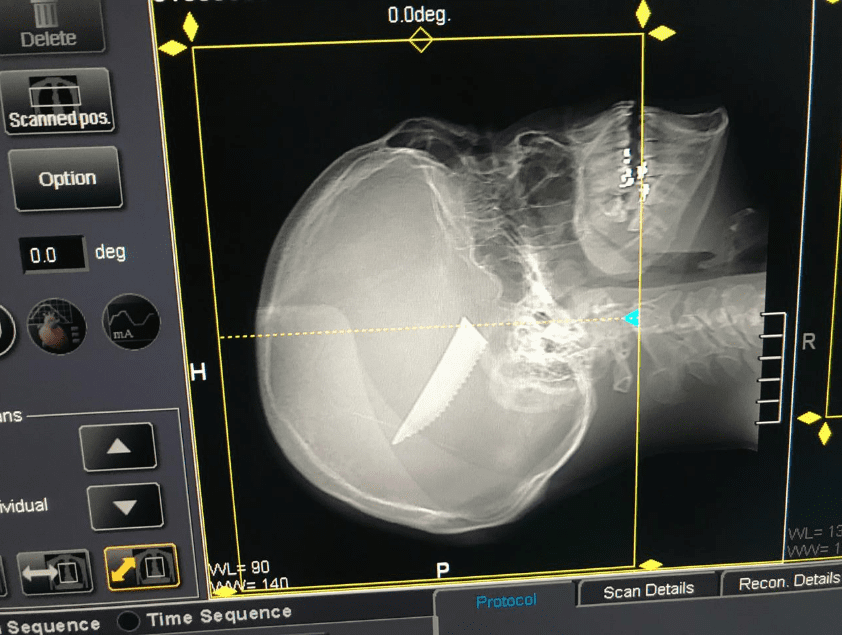

Um homem foi vítima de tentativa de homicídio em Petrolina, no final da noite de ontem (6). Com uma faca cravada na cabeça, o homem recebeu atendimento no Hospital Universitário (HU) e a polícia foi acionada.

Apesar da imagem chocante, a vítima passa bem. O preso foi encaminhado à delegacia, para as providências cabíveis. A motivação do crime não foi informada.

(Foto: 5º BPM/Divulgação)